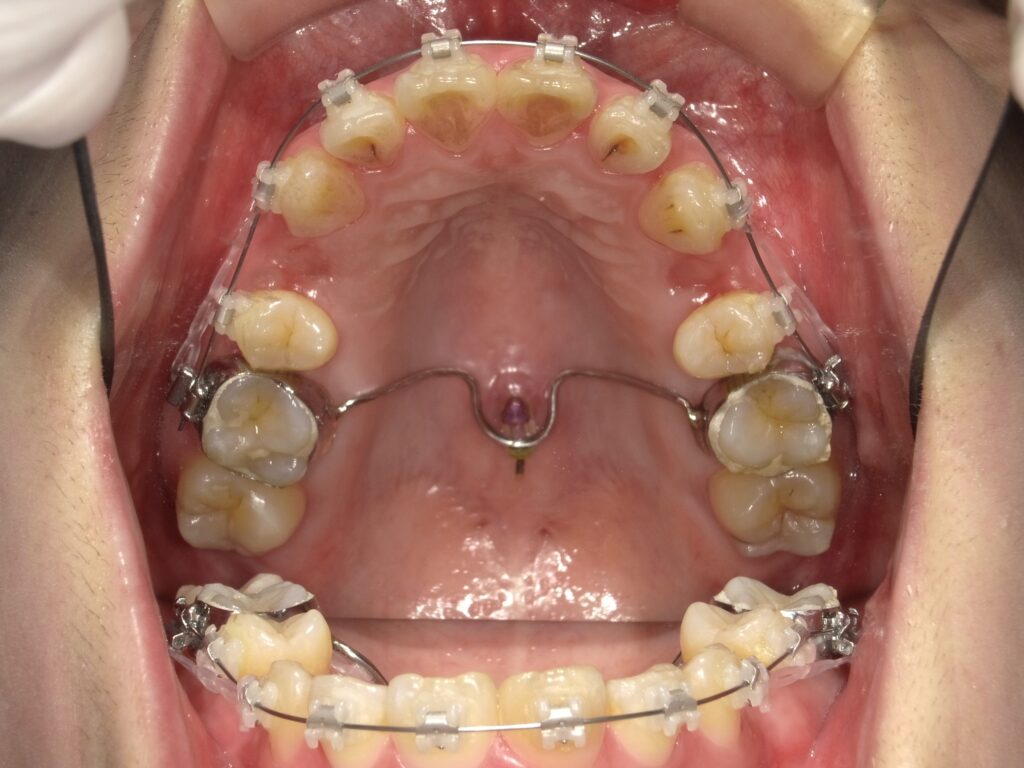

💡 上顎拡大装置(急速拡大装置)

上顎が狭い骨格的な交叉咬合の場合、

「上顎を横に広げる装置を使用します。

これにより、顎の成長方向を正し、将来の顔の歪みを予防できます。